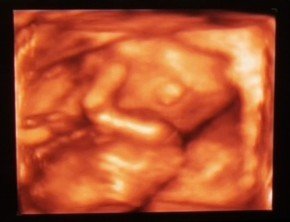

Nekem eddig mindig 3D-t csinaltak, itt mar lehet nincs is 2D.